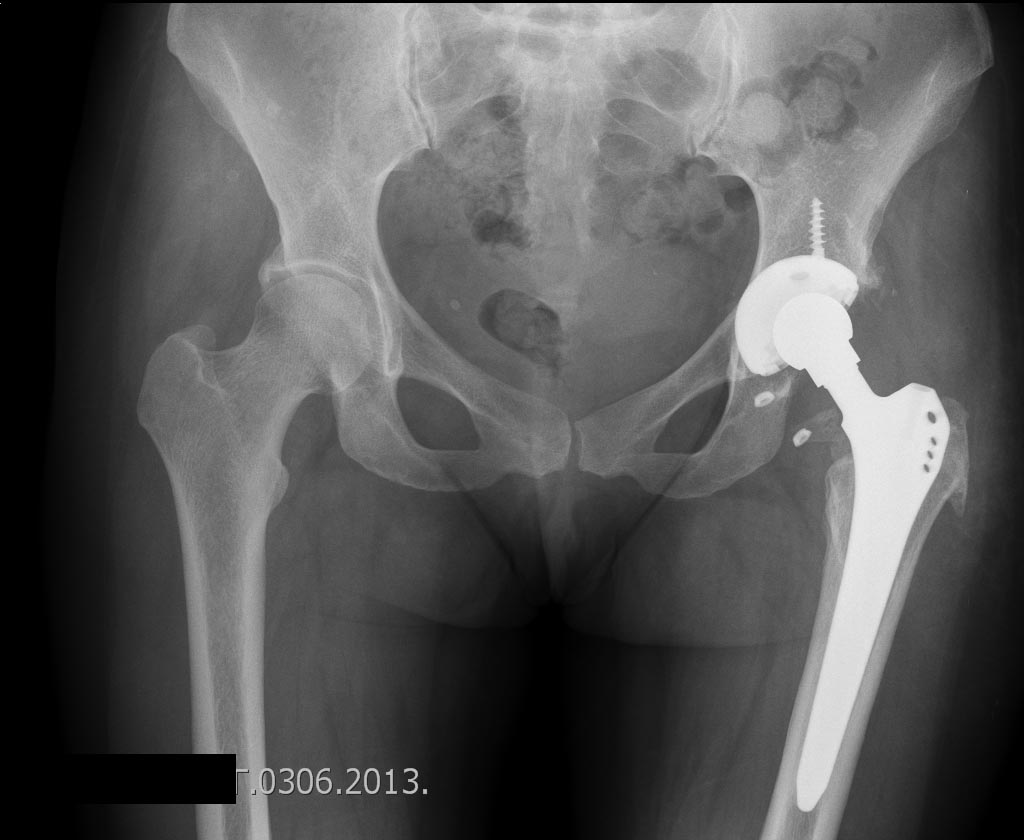

Да конечно чашка была нестабильна.Больная завтра идет домой,вот обзорная

таза.